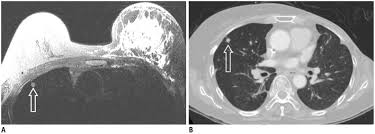

Mri Breast Cancer Detection from breast-cancer.ca Mri of inflammatory breast cancer women's imaging original research. They're often easy to move around (mobile) and may be tender. Inflammatory breast cancer pictures and symptoms Inflammatory breast cancer (ibc) is rare, making up about 2 to 4 percent of breast cancer cases. A small red spot that looks very much like an insect bite or rash can be an early sign of ibc. But not every woman who has been diagnosed with breast cancer needs a breast mri. The features of a malignant breast condition on mri scan are often to do with the outer irregular borders of a lesion. Clinically, inflammatory breast cancer mimics mastitis.

The features of a malignant breast condition on mri scan are often to do with the outer irregular borders of a lesion. Inflammatory breast cancer affects breast tissue and can appear unusually dimpled or thick. Absence of lump or breast mass in a patient suffering from an inflammatory skin condition of the breast, suggests the presence of skin or subcutaneous inflammatory condition caused by either infection or inflammatory breast cancer. The skin looks like the skin of an orange, and may be discolored with painful and itchy breast. The breast is enlarged (often of relatively short onset), indurated, erythematous, warm, and may be tender and painful. But not every woman who has been diagnosed with breast cancer needs a breast mri. What does breast cancer look like on a mammogram? A lump in the breast. Breast mri is sometimes used in women who already have been diagnosed with breast cancer, to help measure the size of the cancer, look for other tumors in the breast, and to check for tumors in the opposite breast. Most cases are invasive ductal carcinomas, which develop in the cells lining the milk ducts and spread throughout the breast. The breast can also be painful in inflammatory breast cancer, but this is not always the case. Evaluating the impact of preoperative breast magnetic resonance imaging on the surgical management of newly diagnosed breast cancers. When the cancer grows into the rest of the body through the blood vessels and lymph vessels, breast cancer spreads.

Inflammatory breast cancer is an an aggressive and fast growing breast cancer in which cancer cells infiltrate the skin and lymph vessels of the breast. They're often easy to move around (mobile) and may be tender. Ibc symptoms are caused by cancer cells blocking lymph vessels in the skin causing the breast to look inflamed. symptoms include breast swelling, purple or red color of the skin, and dimpling or thickening of the skin of the breast so that it may look and feel like an orange peel. Unlike traditional forms of breast cancer, inflammatory breast cancers do not develop unusual lumps within the affected breast. The skin is thickened and edematous, classically with a peau d'orange appearance. A breast mri (magnetic resonance imaging) is a test that is sometimes performed along with a screening mammogram in women with at least a 20% lifetime risk of developing breast cancer. What does breast cancer look like on a mammogram? Mri of breast can help breast cancer diagnosis. Inflammatory breast cancer inflammatory breast cancer is a rare type of breast cancer that develops rapidly, making the affected breast red, swollen and tender. A rash isn't the only visual symptom of inflammatory breast cancer. Inflammatory breast cancer (ibc) is rare, making up about 2 to 4 percent of breast cancer cases. Inflammatory breast cancer pictures and symptoms The skin looks like the skin of an orange, and may be discolored with painful and itchy breast.

It blocks the lymph vessels in the skin of your breast. They're often easy to move around (mobile) and may be tender. When the cancer grows into the rest of the body through the blood vessels and lymph vessels, breast cancer spreads. Breast lesions and chest wall abnormalities 8. Pitting, thickening, or dimpling of skin on the breast, so that it looks like an orange peel, a condition called peau d'orange. Most cases are invasive ductal carcinomas, which develop in the cells lining the milk ducts and spread throughout the breast. To help determine the extent of breast cancer: There may or may not be an underlying palpable mass. Mri of breast can help breast cancer diagnosis. Inflammatory breast cancer pictures show a red and/or swollen breast that appears inflamed. A breast mri usually is performed after you have a. J natl compr canc netw. If these tests don't answer the quest.